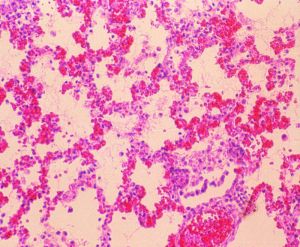

在發病早期可見肺臟壞死、出血,中性粒細胞浸潤,巨噬細胞和血小板激活,血管內有血栓形成等組織病理學變化。肺臟大面積水腫並有纖維素性滲出物。急性期後則主要以巨噬細胞浸潤、壞死灶周圍有大量纖維素性滲出物及纖維素性胸膜炎為特徵。

病豬肺部病變顯微結構包括直接鏡檢、細菌的分離鑑定和血清學診斷。

直接鏡檢:從鼻、支氣管分泌物和肺臟病變部位採取病料塗片或觸片,革蘭氏染色,顯微鏡檢查,如見到多形態的兩極濃染的革蘭氏陰性小球桿菌或纖細桿菌,可進一步鑑定。